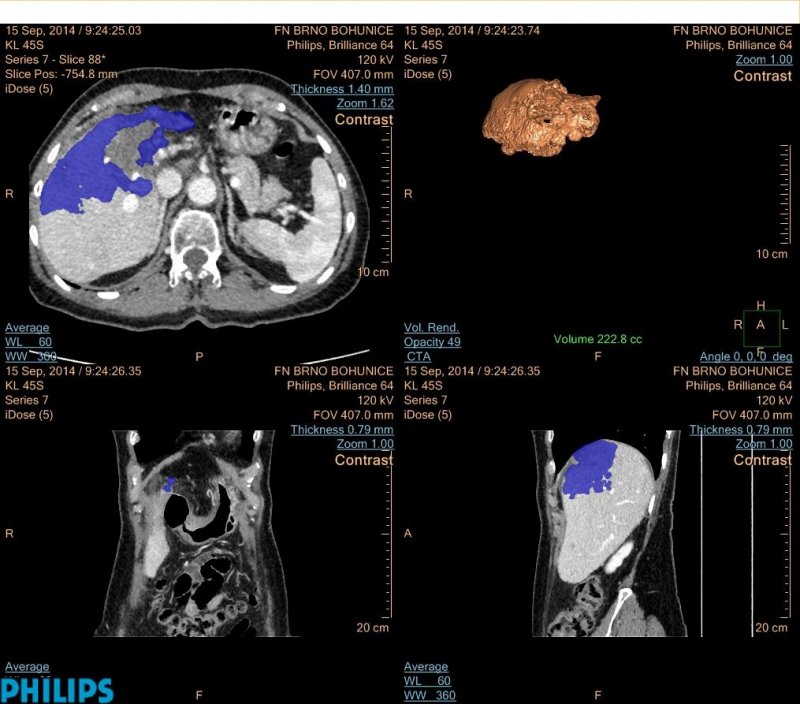

Věnuji se především hodnocení odpovědi na léčbu u hepatocelulárního karcinomu, konkrétně volumetriím po transarteriálních chemoembolizacích. Tato metoda umožňuje zobrazit nádory ve 3D a vypočítat jejich objem, což se jeví přesnější než současné standardní měření v jedné ose. V našem výzkumu se také toto hodnocení ukázalo být jediným faktorem korelace s přežíváním pacientů, což by mohlo ovlivnit jejich léčbu.

Moderní metody terapie jako transarteriální chemoembolizace jsou již i u nás velmi rozšířené. Na našem pracovišti bylo mezi lety 2010 a 2015 provedeno 606 těchto výkonů. Nejedná se však o levnou metodu léčby, proto je důležité stanovit, kteří pacienti z ní mohou opravdu profitovat. Volumetrie se zdá být jedním z ukazatelů účinnosti léčby, tudíž se jedná o velmi slibnou, ač zatím pouze experimentální metodu hodnocení.